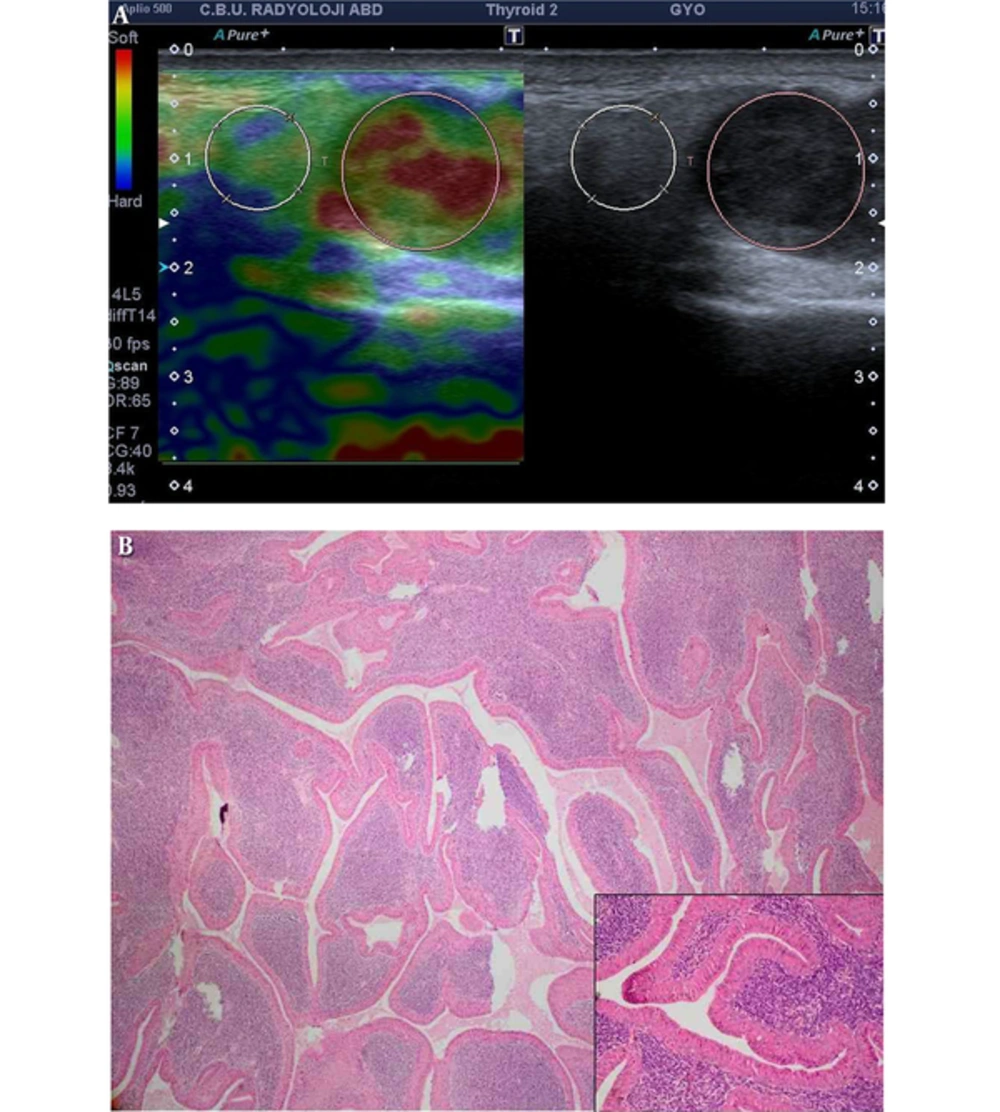

A, Warthin’s tumor: cystic degenerated lobulated hypoechoic solid mass with mixed type vascularization in left parotid gland mass which is predominantly soft. Strain ratio: 0.46, score of 1. B, The tumor is characterized by cystic and papillary appearance with lymphoid proliferation (H&E × 40); inset: papillary projections are lined by oncocytic epithelium which composed of double cell layer (H&E × 200).